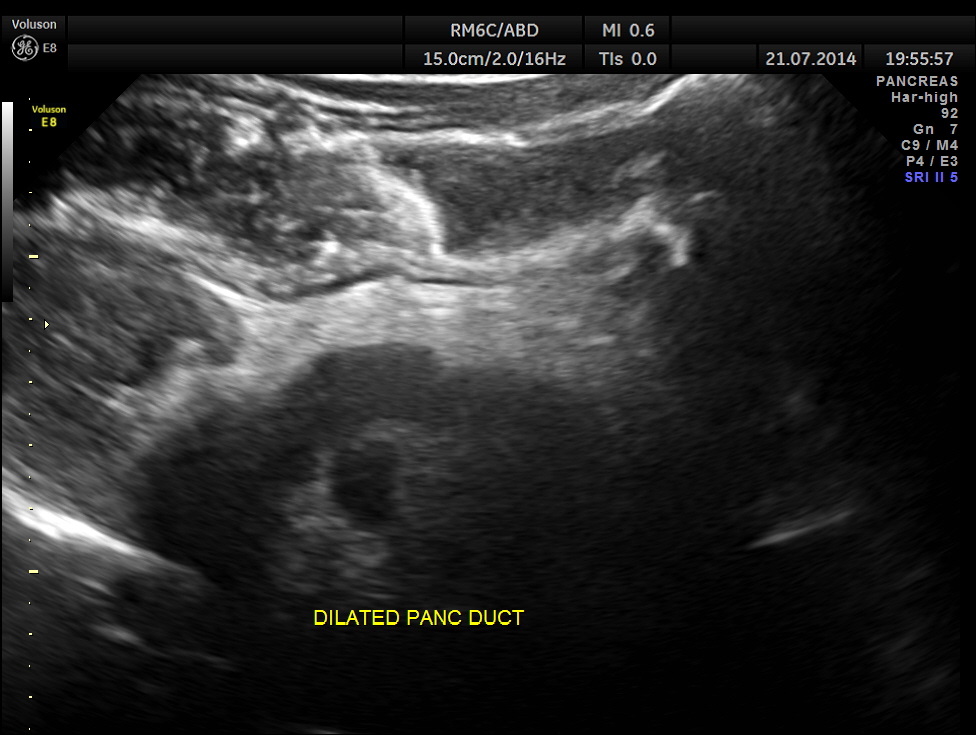

The following pictures show the pancreas.

Pancreatic duct is dilated prominently.

Pancreatic duct dilated.- 12.9 mms.